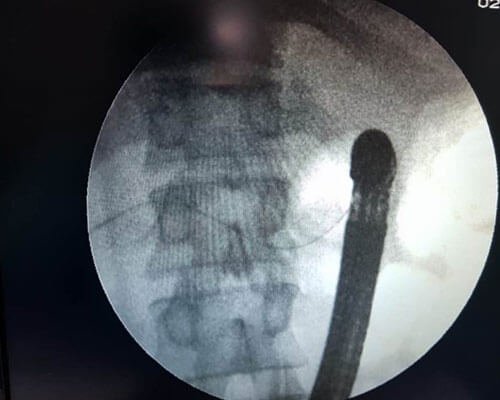

ERCP is performed by the oral route after sedation. During ERCP, bile duct and pancreatic ducts are evaluated after injection of contrast agent, and various therapeutic procedures can be performed

During ERCP stones can be removed form CBD or pancreatic duct and stents can be placed in CBD for treatment of jaundice and in MPD for pain relief